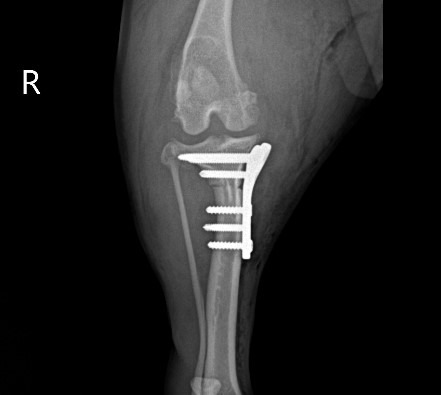

수술 후 방사선 사진 / 출처: 미래동물의료센터

수술 후에는 절개 부위 보호와 관절 안정화를 위해 초기 활동 제한과 절대 안정을 유지했으며, 입원 기간 동안 통증 반응과 보행 상태, 전신 컨디션을 지속적으로 모니터링했습니다. 환자의 수술 후 보행 상태는 매우 원활하게 회복되었습니다.